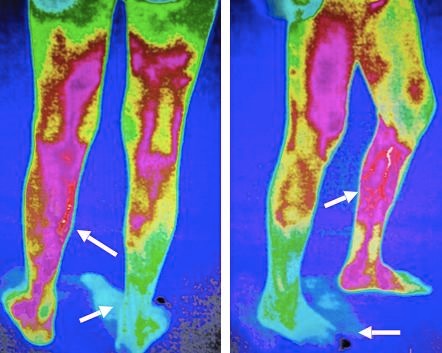

“糖尿病是一种慢性病,患者要充分认识到控制血糖的重要性,不能随意停药,一定要听从专业医生的指导,发现问题及时就医。”王海洋介绍说,足部溃疡是糖尿病常见的主要并发症之一。如果长期血糖控制不力,糖尿病患者更易加剧下肢动脉血管硬化、血管壁增厚、弹性下降,也易形成血栓,造成下肢血管闭塞、肢端神经损伤,导致下肢组织病变。糖尿病人如何才能及早发现是否存在下肢血管病变?王海洋说,该院血管外科将红外线热成像检测技术应用到血管筛查领域。

红外检测对体表温度感应灵敏度高,在血管病变筛查中可起到早期预警的作用“这种检测技术是由钟南山院士团队研发出来的。对体表温度感应的灵敏度高,在血管病变筛查中可起到早期预警的作用,而且无创无辐射。”王海洋建议有糖尿病史的患者定期进行血管筛查,警惕血管病变。如果下肢动脉血流通畅,在血糖控制平稳的情况下,建议每年做1~2次血管筛查,以便及早发现血管隐患及早干预。